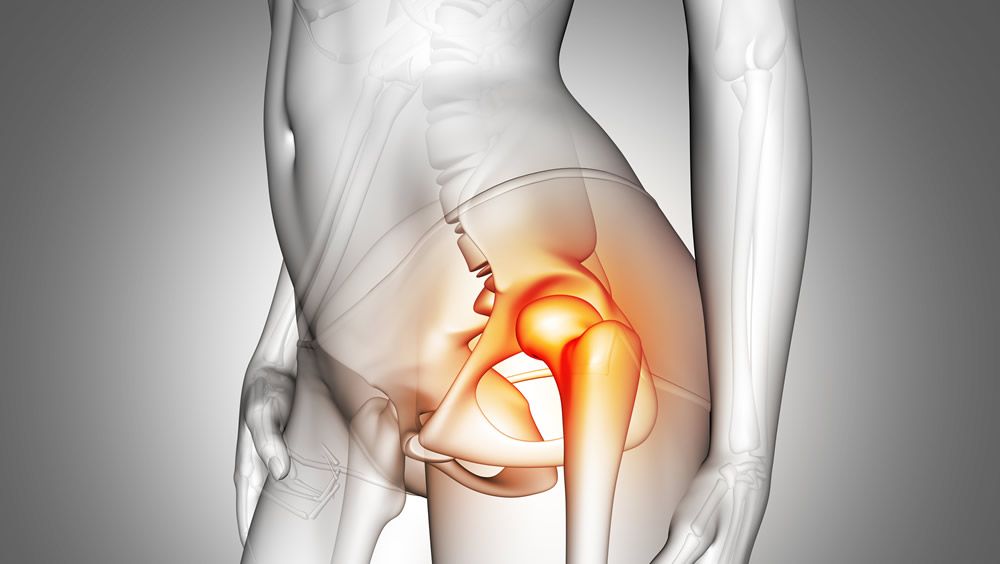

Se trata de un sistema de tornillos de interferencia Citrelock con tecnología de material Citregen, un polímero sintético bioabsorbible termoestable de nueva generación ahora aprobado por la FDA. El sistema Citrelock está diseñado para unir tejido durante cirugías ortopédicas, como la fijación de ligamentos o la reparación de tejido de injerto de tendón del hombro, codo, muñeca, mano, rodilla, tobillo y extremidades del pie.